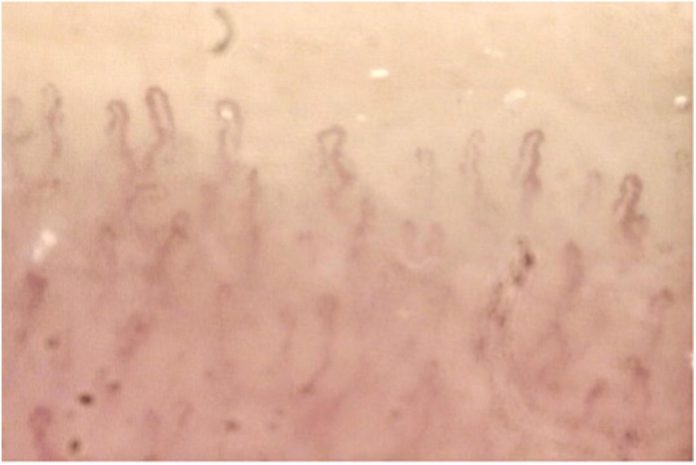

Η νόσος Αδαμαντιάδη-Behcet είναι αγγειίτιδα μικρών αγγείων, αλλά μπορεί να προσβάλλει και αγγεία μεσαίου ή μεγάλου μεγέθους. Είναι συχνότερη σε χώρες της Ανατολικής Μεσογείου, της Μέσης Ανατολής και της Ανατολικής Ασίας, προσβάλλει, κυρίως, νέους ενήλικες και η μέση ηλικία έναρξης της νόσου είναι μεταξύ 25-30 ετών.

• Φλεγμονή στο μάτι, όπως π.χ. ιριδοκυκλίτιδα που εκδηλώνεται με πόνο και κοκκίνισμα στο μάτι (συνήθως, αμφοττερόπλευρη).